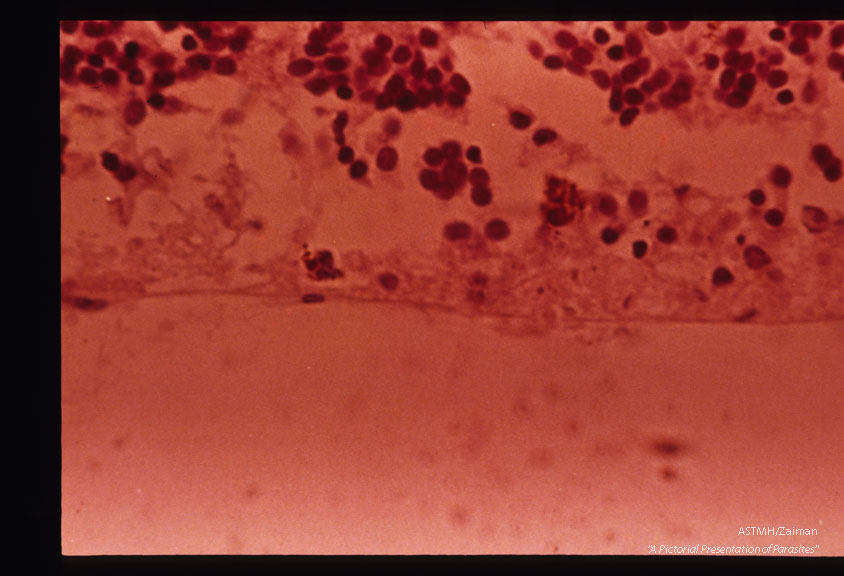

Toxoplasmic retinochoroiditis with Toxoplasma groups in center. H&E stain.

Description: Toxoplasmic retinochoroiditis with Toxoplasma groups in center. H&E stain.